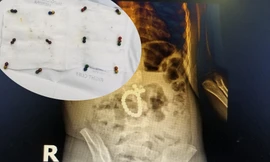

TPO - Bệnh viện Sản nhi Nghệ An vừa phẫu thuật, cấp cứu cho một bé N.T.T (3 tuổi, trú tại TP Vinh) bị thủng tá tràng, ruột do nuốt phải 25 viên bi nam châm.

Đến Bệnh viện Đa khoa MEDLATEC khám trong tình trạng đau bụng nhiều ngày không rõ nguyên nhân, gia đình bé vô cùng sững sờ biết nguyên nhân con có nguy cơ thủng ruột. May mắn bé được ê-kíp cấp cứu của bệnh viện xử trí kịp thời, qua cơn nguy kịch.